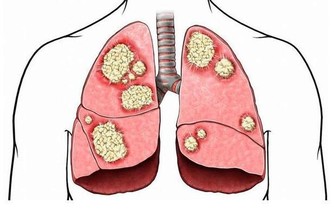

目前,在一線大城市,腸癌有超越肺癌成為新“癌王”的勢頭。今年發布的《中國體檢人群結直腸癌及癌前病變白皮書(2020年版)》指出,結直腸癌是我國高發癌症,2015年,中國新發患者38.8萬例,死亡約18.7萬例。換言之,平均每10分鐘,約7人被診斷為結直腸癌,約4人因此去世。這也為我們敲響警鐘,應當學會腸癌的預防。腸癌有沒“光臨”你,摸摸這處就知道!

其實,腸癌是便血的另一個重要原因,如結腸下段或直腸癌糜爛壞死,可出現黏液膿血便。